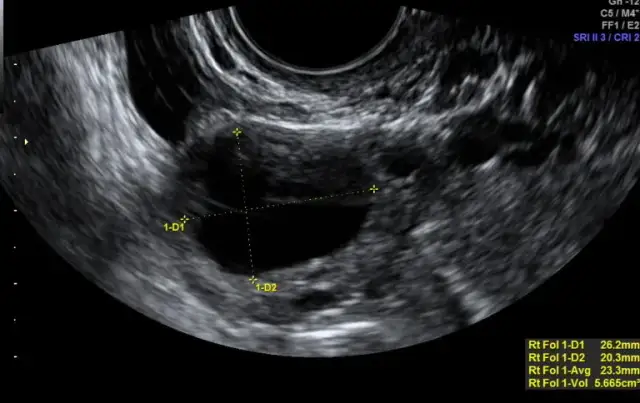

Zobacz, co można zaobserwować na USG po owulacji. Dowiedz się o kluczowych zmianach w jajnikach i macicy, które wpływają na płodność.